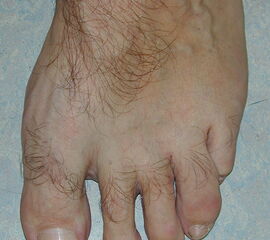

Vorfußbreite

Eine Verbreiterung des Vorfußes wird als Spreizfuß bezeichnet. Ursächlich ist meist eine Deviation des ersten Metatarsale nach medial und/oder eine Abweichung des fünften Metatarsale nach lateral. Die Abweichung kann im Röntgenbild quantifiziert werden. Der Winkel zwischen Os metatarsale I und II wird als pathologisch zu bezeichnet, wenn er in der belasteten dorsoplantaren Röntgenaufnahme 9° überscheitet. Der Intermetatarsalwinkel IV/V wird ab einem Wert von mehr als 8° als erhöht.

Abbildung 15: Schwere Spreizfußdeformität (M. Walther).

Abbildung 16: Belastetes dorsoplantares Röntgenbild des Fußes. Zur Beurteilung des Spreizfußes wird der Intermetatarsalwinkel I/II (grüne Linien - Norm < 9 Grad) und der Intermetatarsalwinkel IV/V (blaue Linien - Norm < 8°) bestimmt. Die Abweichung der Großzehe ist durch den Hallux valgus Winkel definiert (grüne/rote Linie), eine Fehlstellung innerhalb der Großzehe durch den Interphalangealwinkel (rote/gelbe Linie) (M. Walther).

Zum Lesen der Bildbeschreibung und zur Vollansicht bitte die Bilder anklicken.